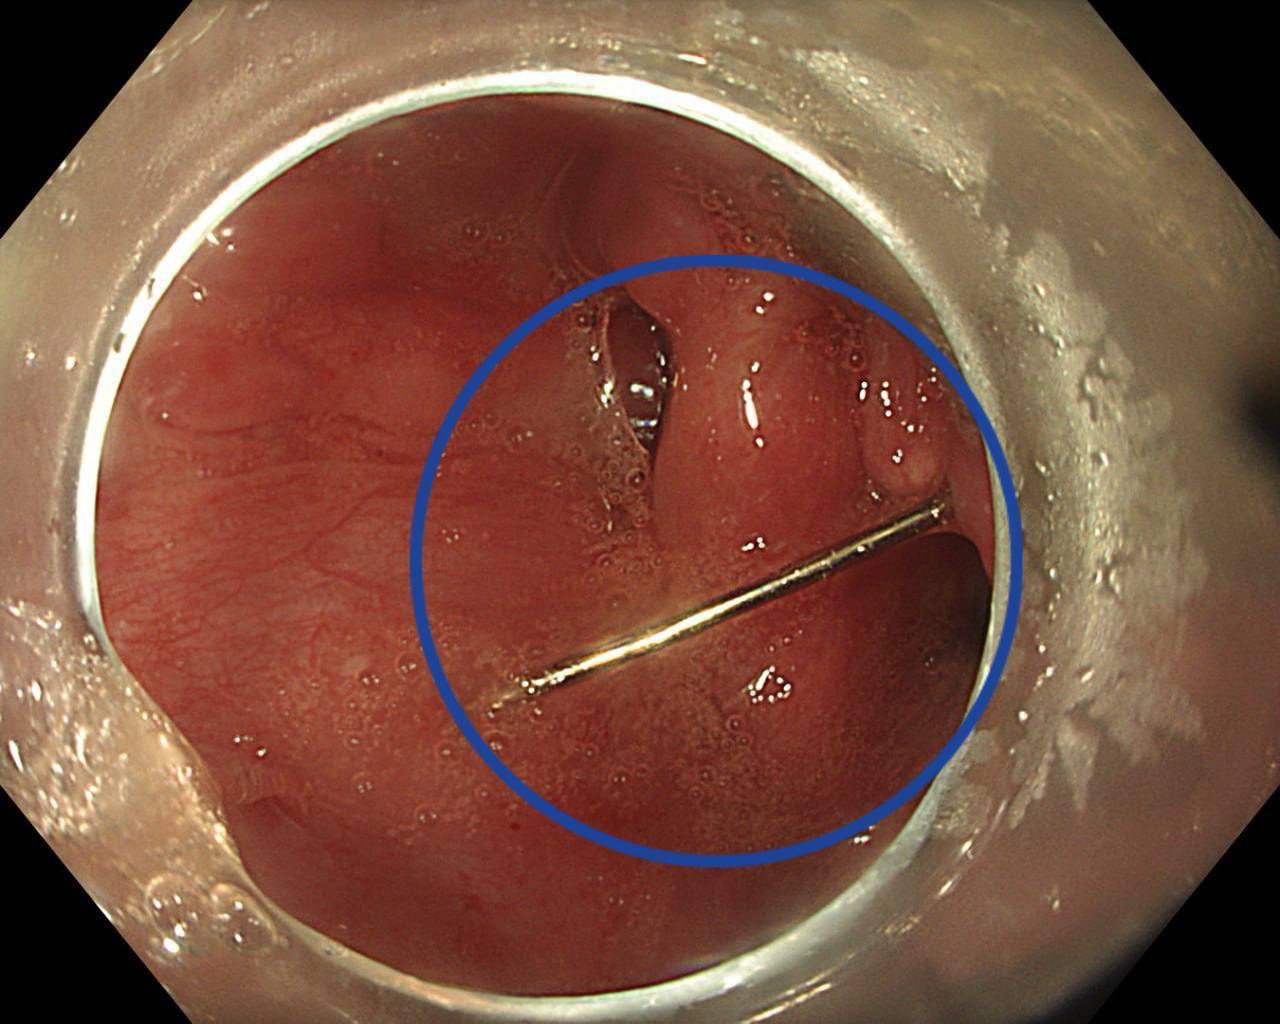

В Подмосковье 15 летняя девочка из любопытства проглотила иглу Родители сразу обратились за медицинской помощью Пациентку доставили в Детский научно клинический центр им Л М Рошаля с жалобами на сильную боль в горле рвоту с кровью и затрудненное глотание При обследовании врачи обнаружили инородное тело Операция прошла успешно и была проведена без единого разреза сообщил заведующий отделением эндоскопии Александр Иноземцев Подпишись на нас в МАХ

Специалисты ДНКЦ имени Л М Рошаля извлекли из гортаноглотки подростка иглу В учреждение здравоохранения бригадой скорой помощи была доставлена 15 летняя пациентка с жалобами на сильную боль в горле рвоту с кровью и затрудненное глотание Как сообщает пресс служба Минздрава Подмосковья девочка случайно проглотила иглу после чего родители немедленно обратились за медицинской помощью В Детском научно клиническом центре им Л М Рошаля пациентке провели рентгенографию и гастроскопию Обследования подтвердили что в гортаноглотке находилось инородное тело Подростка незамедлительно госпитализировали в хирургическое отделение По словам заведующего отделением эндоскопических методов диагностики и лечения Александра Иноземцева если вовремя не оказать помощь в такой ситуации это может привести к тяжелым последствиям кровотечению или перфорации гортаноглотки Мы выполнили пациентке эндоскопическую операцию по удалению инородного тела с помощью эндоскопических щипцов клинка для прямой ларингоскопии и хирургического зажима аккуратно захватили иголку и извлекли из гортаноглотки Операция прошла успешно и без единого разреза сказал врач Игла не успела навредить слизистой девочки Подросток чувствует себя хорошо и готовится к выписке Медики напоминают если ребенок проглотил или вдохнул инородное тело следует немедленно вызвать скорую помощь и не пытаться извлечь его самостоятельно